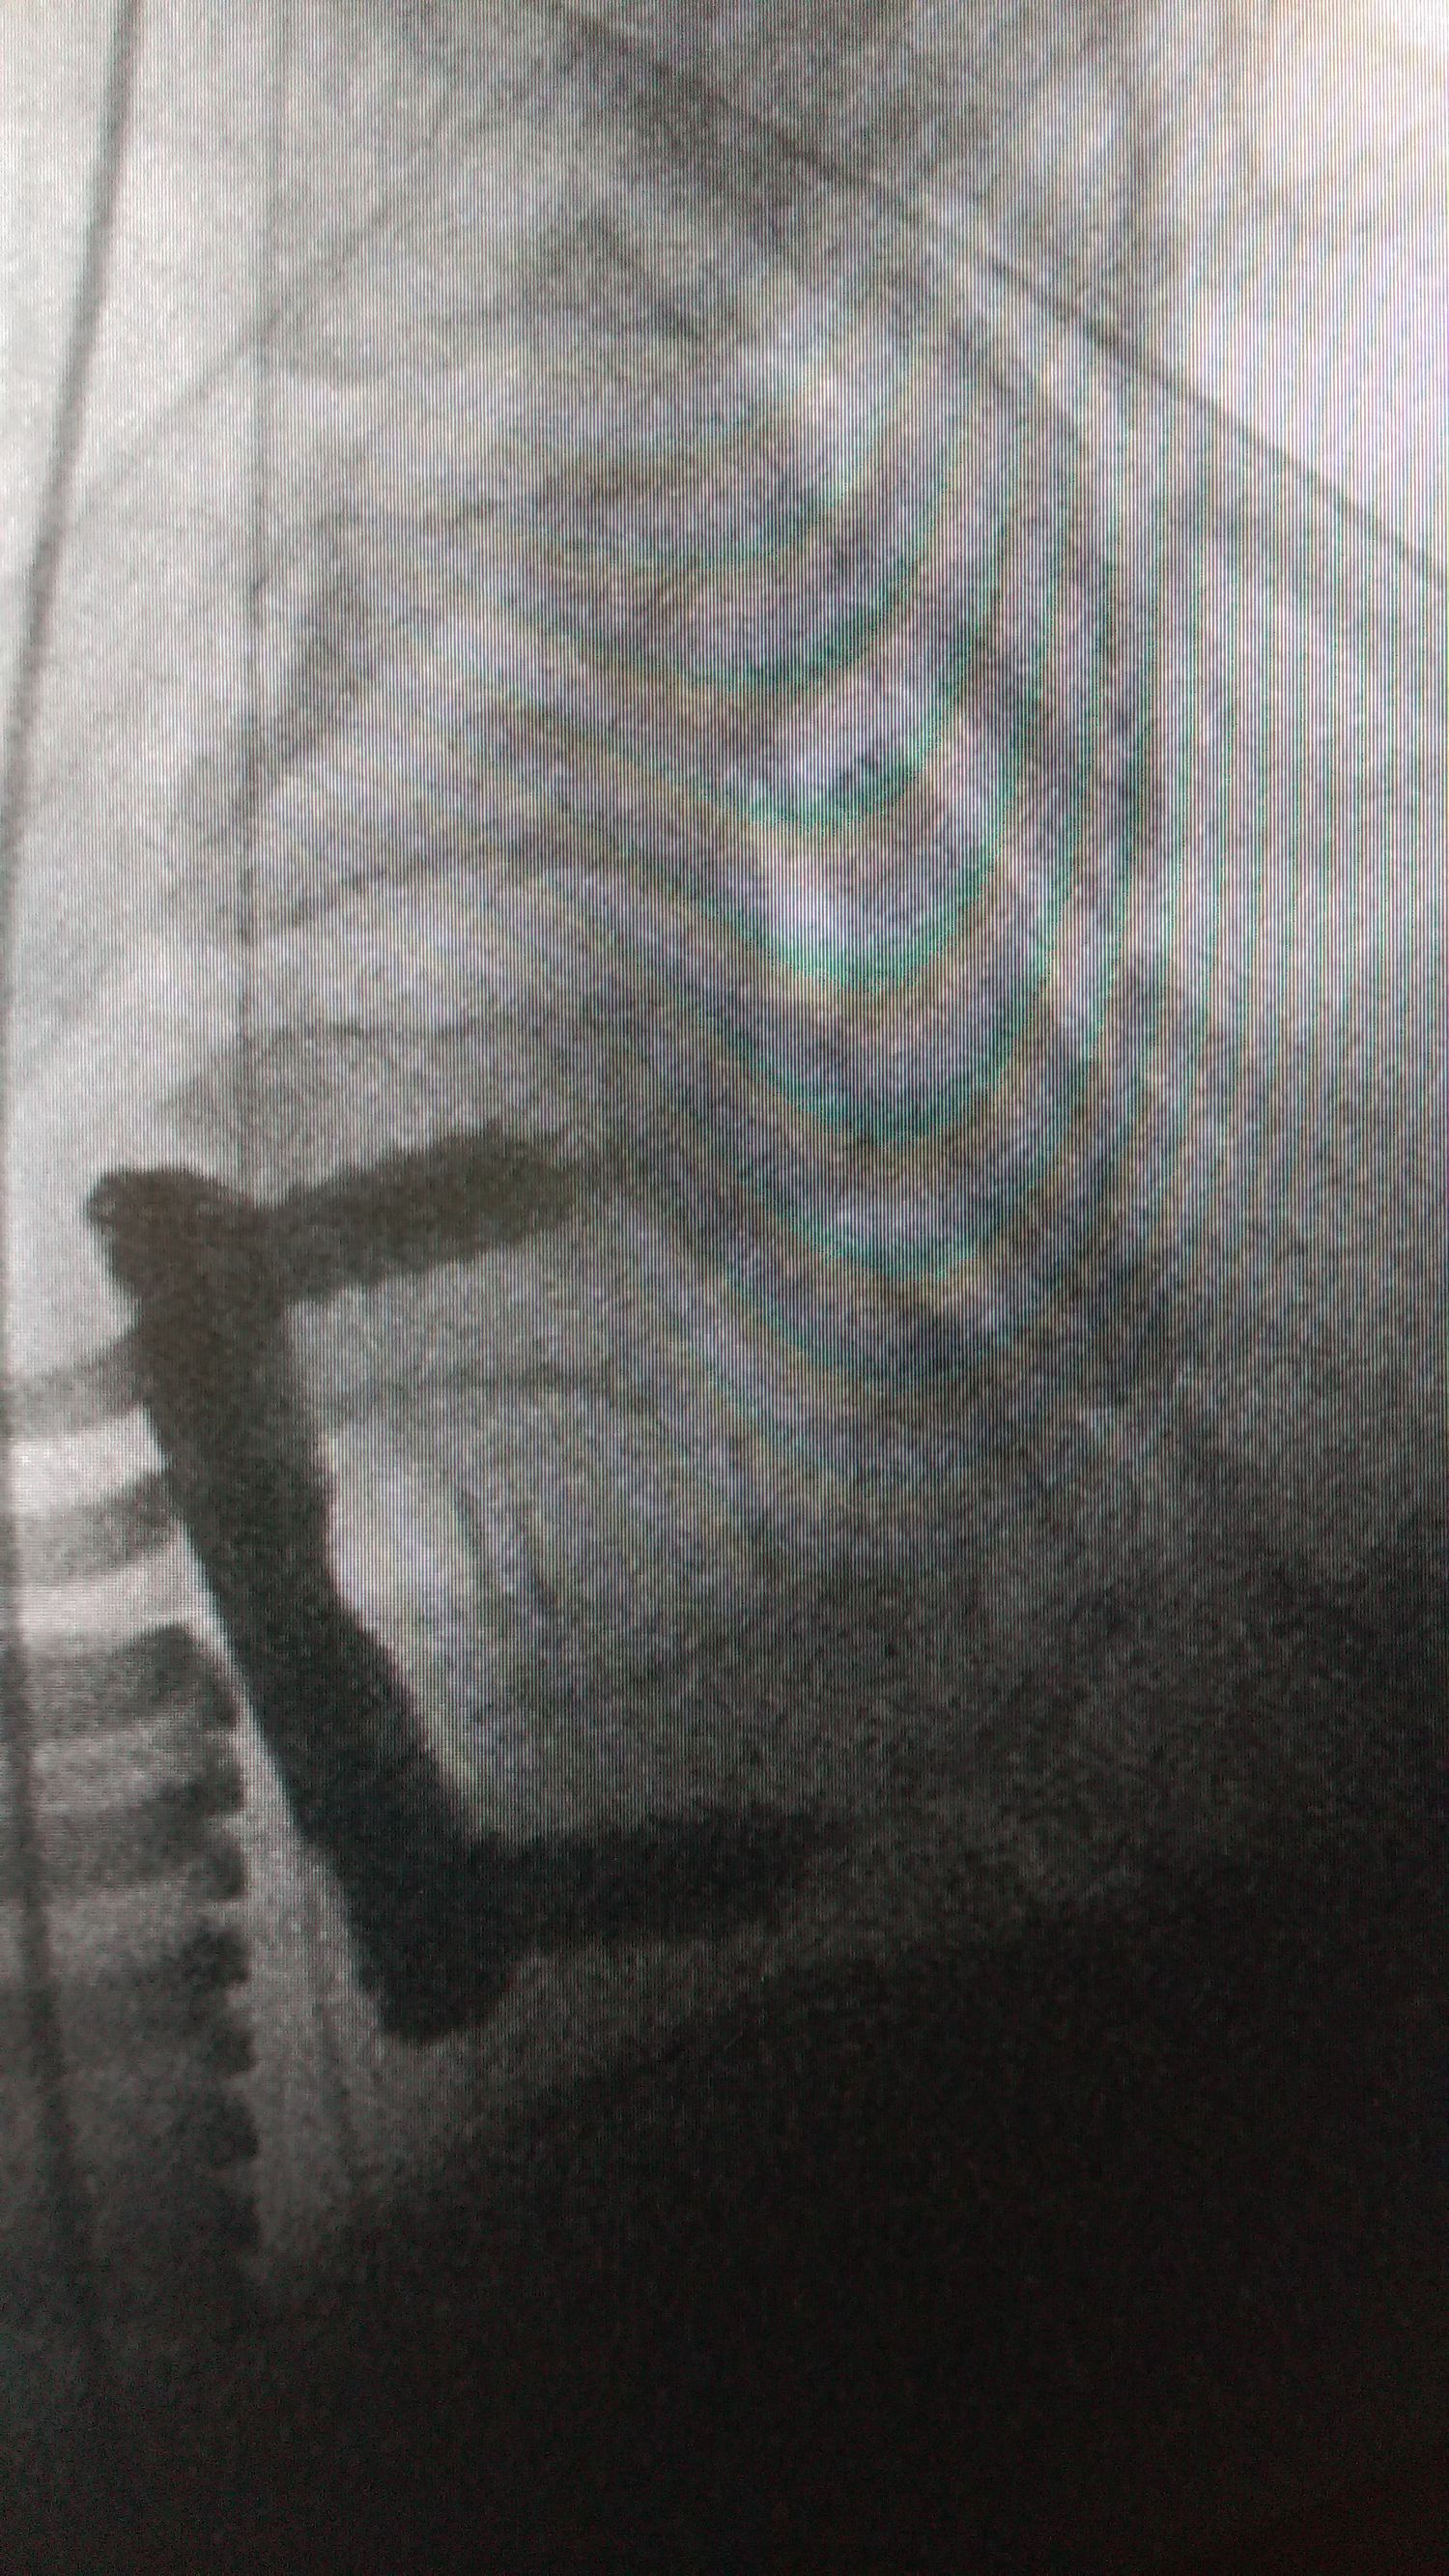

Διεγχειρητική ακτινογραφία ανάταξης και σπονδυλοδεσίας Α6-7.

Μετεγχειρητική μαγνητική τομογραφία με τον ασθενή σε σταδιακή βελτίωση και ίαση.

Η βελτίωση του ασθενούς μετεγχειρητικά ήταν σταδιακή και εντυπωσιακή. Ακολούθησε ειδικό πρόγραμμα μηνών σε κέντρο αποκατάστασης και αναμένεται πλήρης λειτουργικότητα.